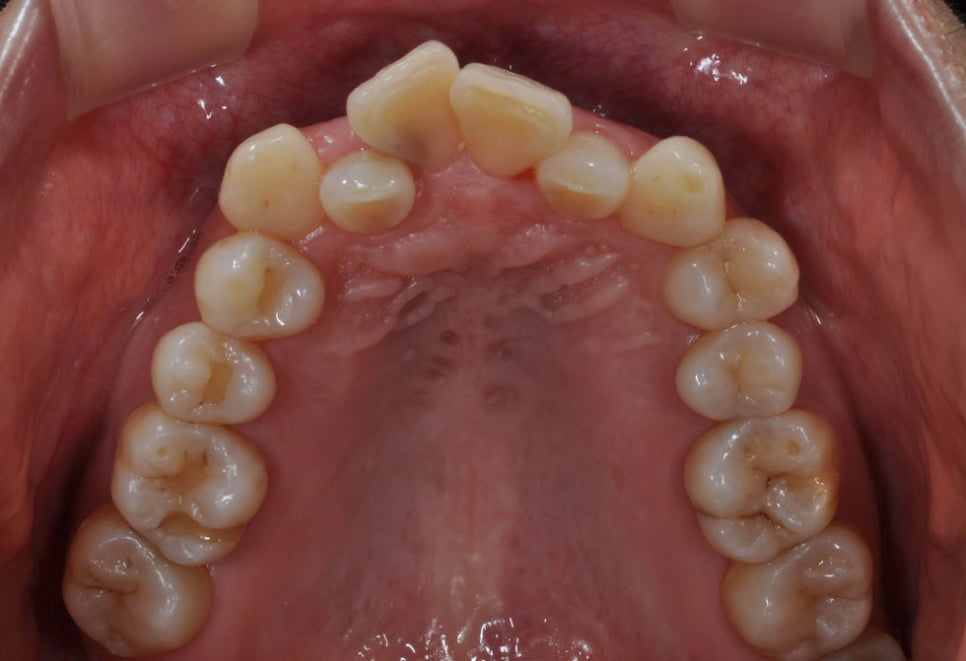

말합니다. 위 사진과 같이 거의 보이지 않는

교정 장치를 순서대로 끼는 것만으로

치아가 교정되는 것입니다.

교정이 필요한 대상은?

치아 배열이 올곧지 못하고 울퉁불퉁한 경우,

덧니가 있는 경우, 앞니가 튀어나온 경우나

주걱턱, 돌출입 등에 교정 치료가

적용될 수 있습니다.

여러 개의 치아가 방향이 틀어지거나

겹치는 경우, 어금니의 교합이 맞지 않아

배열이 바르지 못한 경우, 치아 사이의

공간이 있는 경우, 선천적으로 악궁의

크기가 작아 배열 공간이 부족한 경우,

치아가 쓰러져 있거나 정중선이 맞지

않는 경우에 치열 교정 치료가

필요할 수 있습니다.